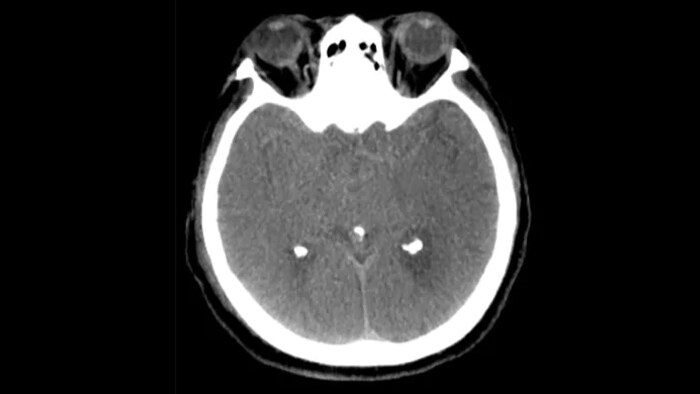

3D visualization and measurement solution

SmartCT Soft Tissue Helical*

Improved neuro CT-like cone beam CT images (CBCT) to identify soft tissue changes in the angio suite. An advanced protocol with dual-axis acquisition trajectory and improved reconstruction software results in improved image appearance, compared to conventional CBCT acquisition techniques.